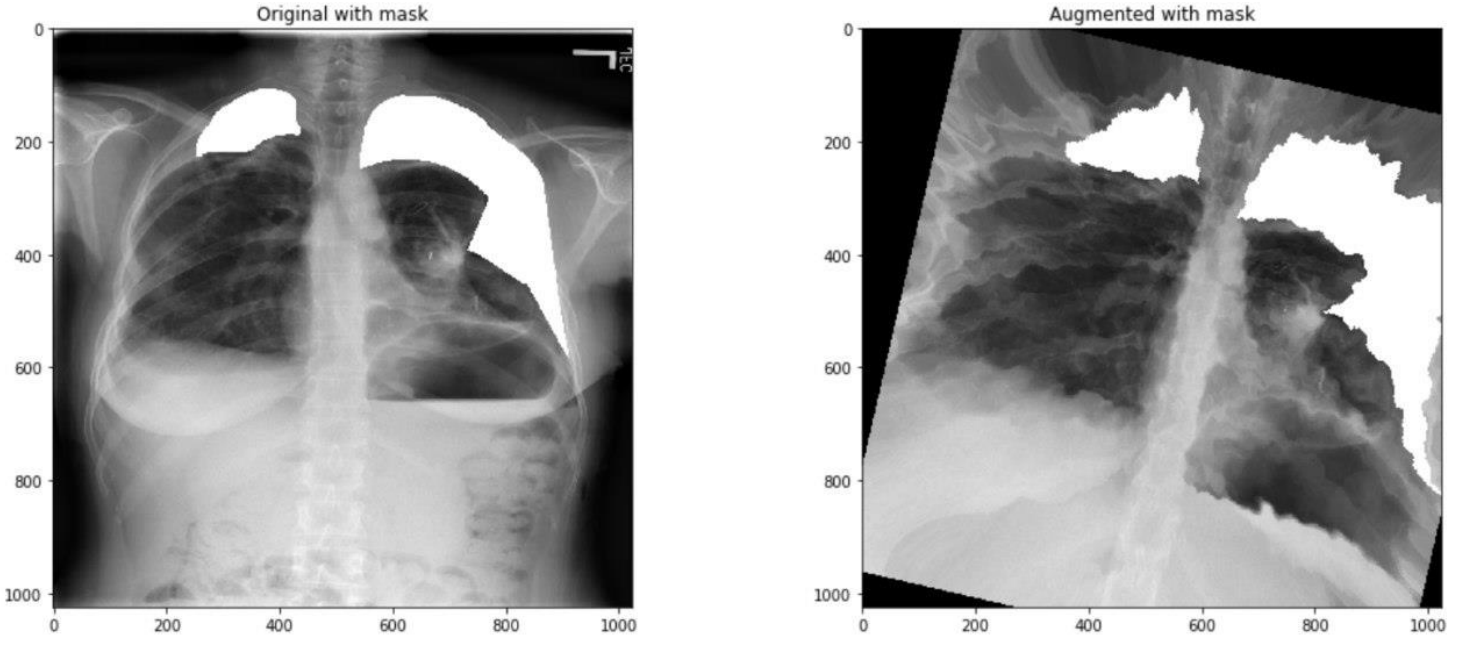

这里模型的输入是1024X1024X3的胸片和1024X1024X1的mask。作者直接使用了图像增强库 albumentations 对数据进行增强,作者使用了一个较为复杂的方案:以固定顺序对图像进行不同的变换,并且给予每种方法一定的概率,使增强方法的运用随机化。具体如下:

- HorizontalFlip:0.5

- OneOf:0.3

- RandomContrast:0.5

- RandomGamma:0.5

- RandomBrightness:0.5

- OneOf:0.3

- ElasticTransform:0.5

- GridDistortion:0.5

- OpticalDistortion:0.5

- ShiftScaleRotate:0.5

上面小数表示此增强方法运用的概率,OneOf表示在其子方法中选择一个。

需要注意的是,这里有2个OneOf,第一个OneOf下面的增强方法主要对图像的亮度、对比度等进行调整,而第二个OneOf下面的增强方法主要对图像的形状进行调整。可以看几个例子。

因为训练模型分成四个阶段,每个阶段使用的数据是一样的,使用一定概率给图像做增强,实际上保证了每个阶段实际参加训练的数据都不完全一样。